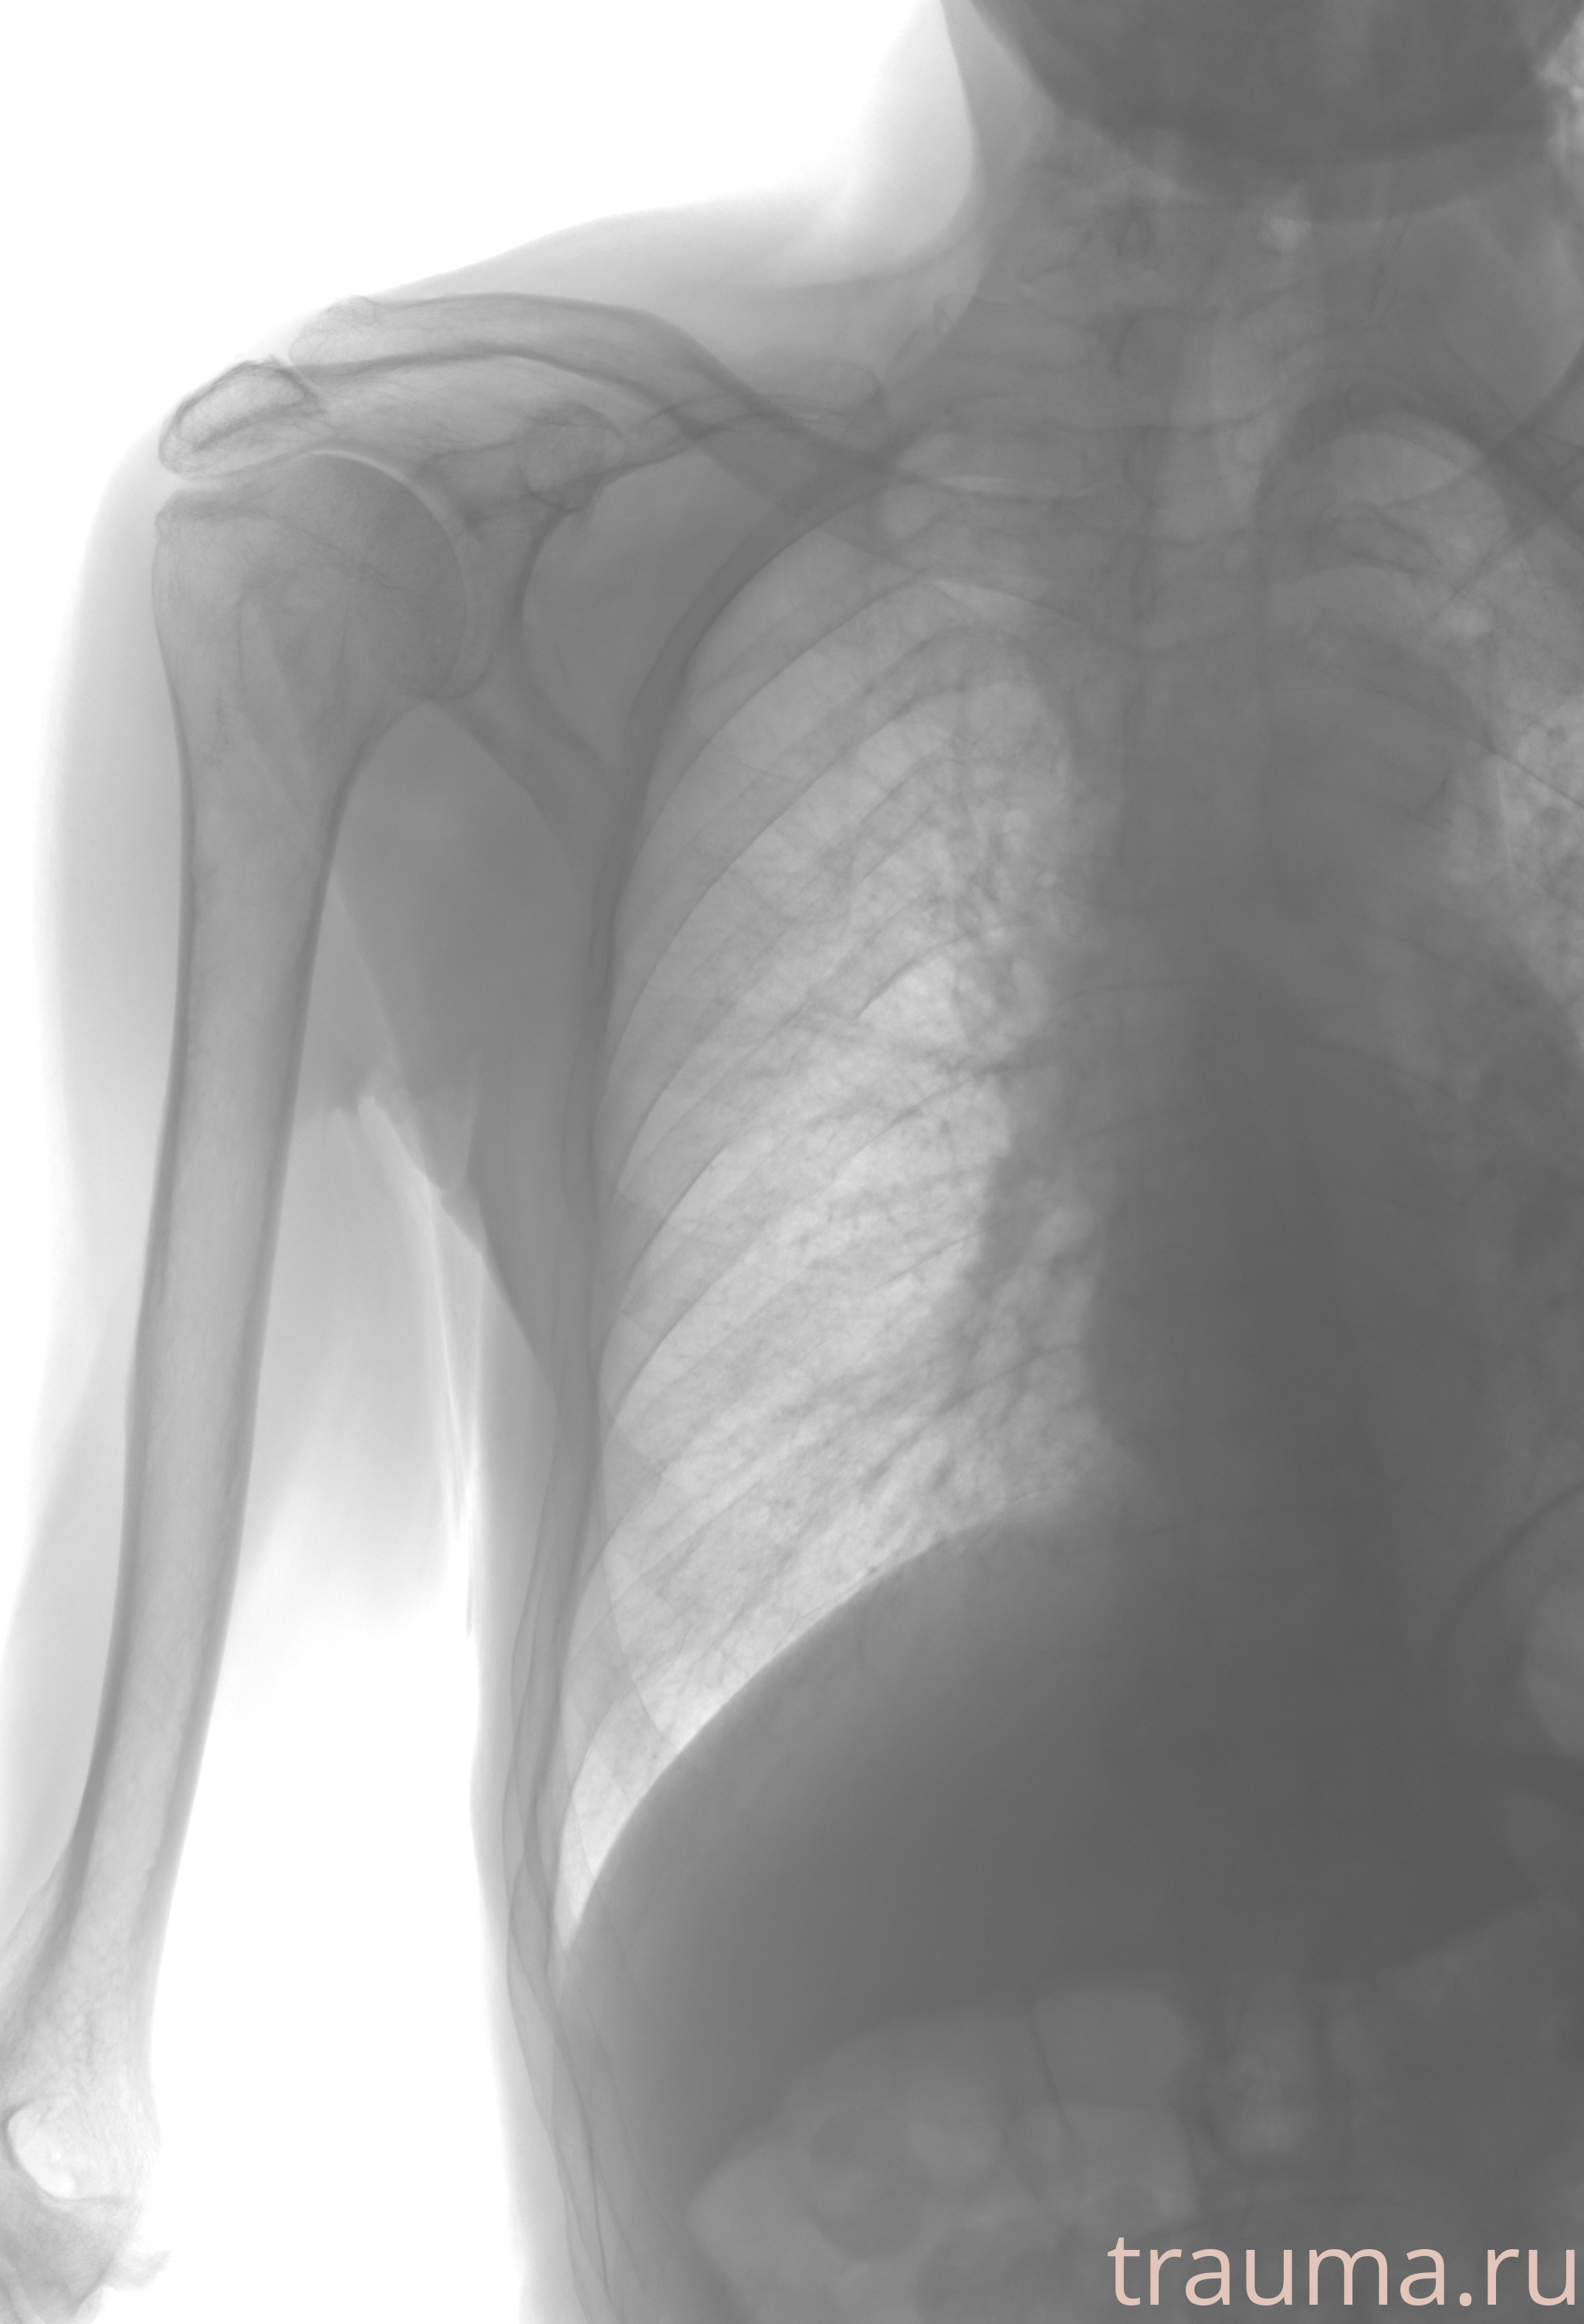

Рентгенограммы

Рентген на дому: по вашему адресу приезжает врач-рентгенолог, травматолог-ортопед с мобильным рентгеновским аппаратом, проводит диагностику травмы или заболевания, делает необходимые рентгенограммы, дает рекомендации по дальнейшему лечению. Получить качественные снимки в домашних условиях возможно благодаря уникальной методике, разработанной МосРентген Центром для института  Склифосовского